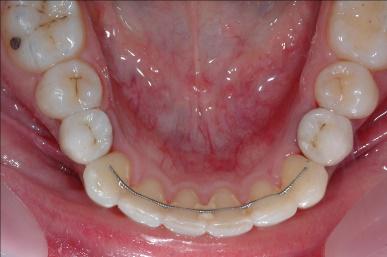

La technique linguale

Totalement invisible les attaches orthodontiques sont collées sur la face linguale